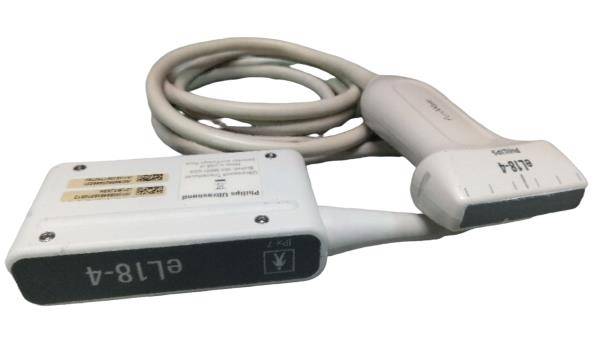

Philips L9-3 Linear Ultrasound Transducer Probe

Sale price$ 1,438.28